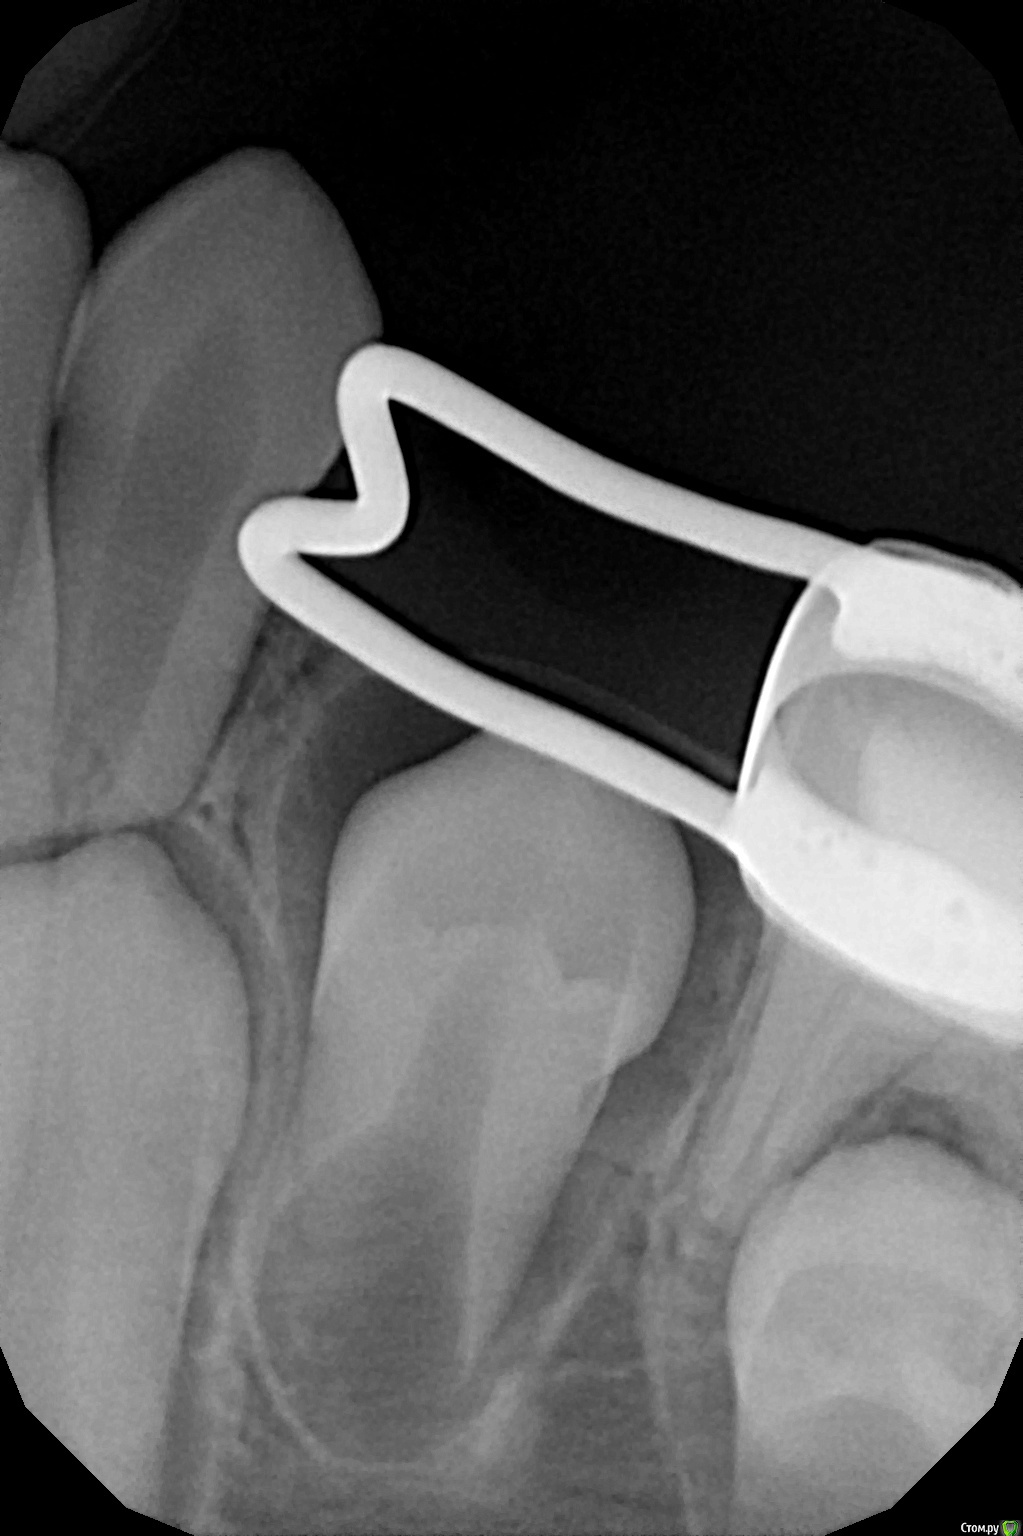

crown Опубликовано 7 апреля, 2017 Поделиться Опубликовано 7 апреля, 2017 8,5 лет, 3.4 полностью в кости, визуально места для зуба 3.4 очень много. Когда снимать конструкцию и возможны ли в дальнейшем тремы? Ссылка на комментарий

Yana guapa Опубликовано 7 апреля, 2017 Поделиться Опубликовано 7 апреля, 2017 как зуб покажется - тогда и снимать. кольцо не мешает началу прорезывания Ссылка на комментарий